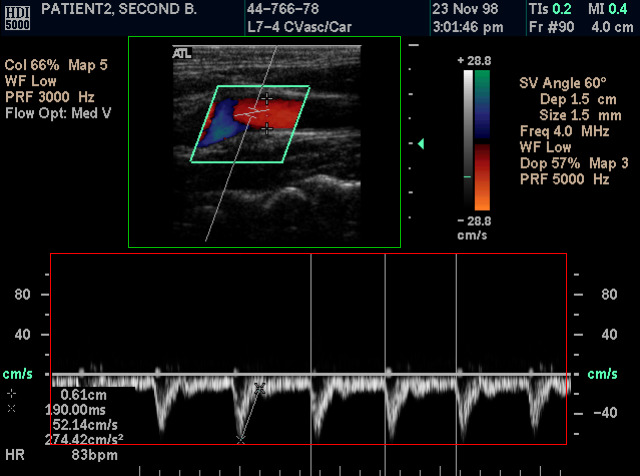

Take calibrated Ultrasound measurements

The program supports the Ultrasound Region Calibration Module (0018, 6011), and it can take calibrated distance and area measurements in ultrasound DICOM files.

When the user selects the distance measurement tool, one or more rectangles appear on the image. Each one of these rectangles represents a calibrated region. The active region has a green color and the inactive regions have a red color. Within the active (green) region the mouse cursor has a cross shape, and within the inactive (red) region has an arrow shape. The user can take measurements in the active region.

By clicking the right mouse button, a pop-up menu appears and allows the user to select the active region.

By selecting the menu command "View US Region Details...", a dialog box appears and it displays the type, the units and the delta of the active region.

The user can easily check the accuracy of the measurements by taking the same measurement in the ultrasound machine and in the program.